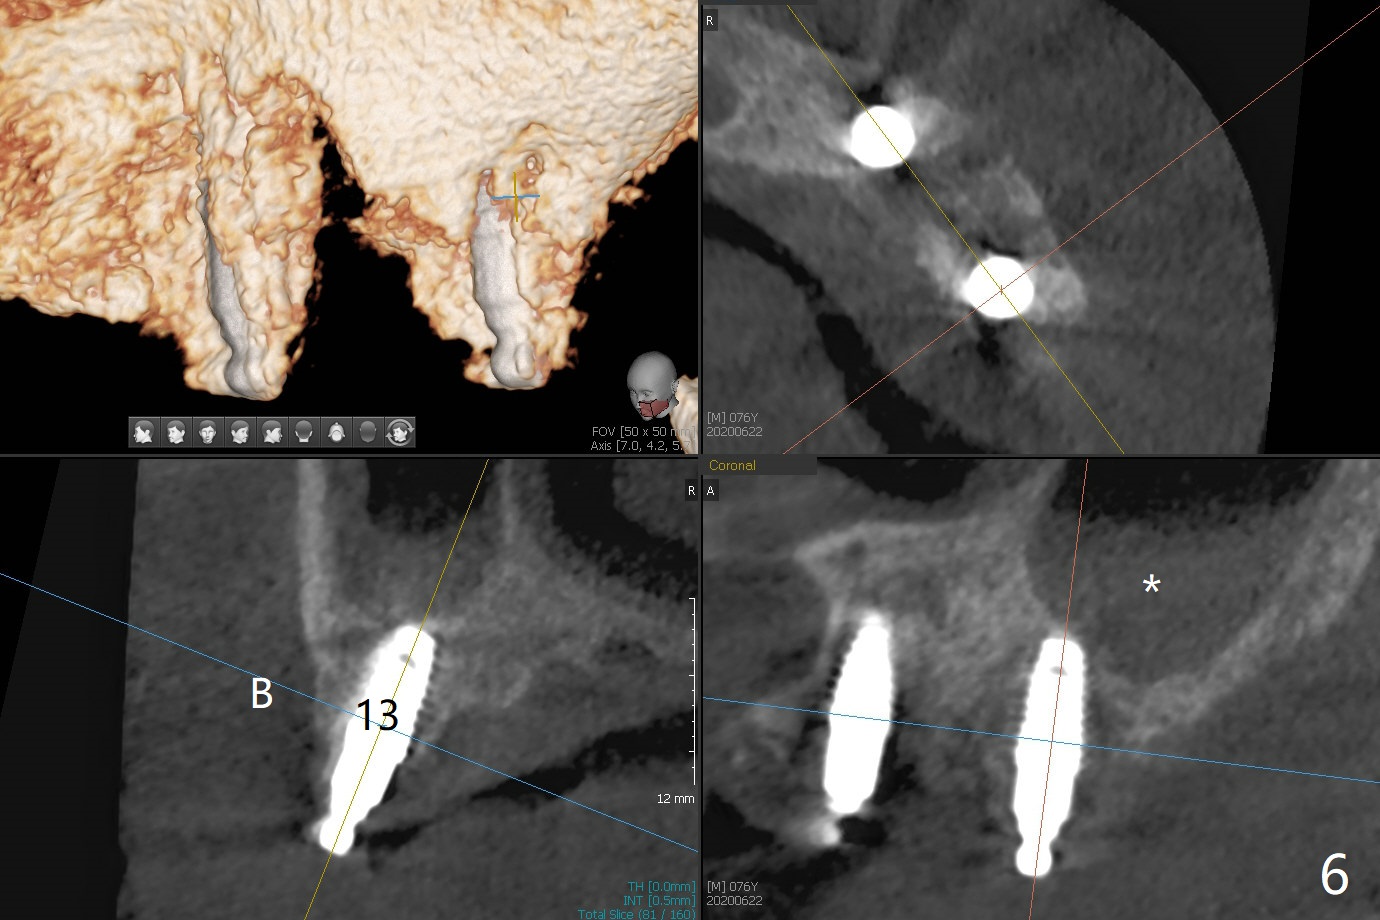

Osteotomy at #13 starts blindly (no incision or tissue punch) with bone expanders. After insertion of parallel pins, intraop CT shows that it is palatal with apparently buccal low bone density (Fig.1); the osteotomy for implant (Fig.2 green) should be shifted buccal and tilted mesial (red, parallel to #11) with incision. In contrast the position, trajectory and depth (Fig.3 <) of the initial osteotomy are acceptable at #11. The implant will be placed as it is (Fig.4). After taking a postop PA (Fig.5), the implant at #11 is placed a little deeper to make sure its slightly subcrestal placement (including distal incision at #11). Following placement of 3.5x4 and 3 mm ball abutments at #11 and 13, cortical allograft with PRF is placed around the implants, especially buccal (Fig.6,7 <). After suturing, the profile of the ball abutments is too low for RPD retention. Due to gravity other than bone density, the number of ball abutments for the maxilla should be more than for the mandible. Soft reline is done to the patient's satisfaction. The retention of the upper RPD after soft reline is satisfactory without pain 7 days postop (Fig.8). The implant at #13 is loose nearly 3 months postop (Fig.9 *: bone loss). The implant is removed while the ball abutment is untightened; the sinus floor is present. It appears that a longer and larger implant is necessary; a 4.5x10 mm dummy implant is unable to be seated deep or achieve primary stability (Fig.10). After sinus lift with 3 mm Bicon osteotome without bone graft, the dummy implant accomplishes the 2 tasks mentioned above (Fig.11). However there is no corresponding definitive implant in stock. Implant system needs to be changed; with a change in implant driver, the depth control is lost. The final implant is placed deep (Fig.12). With back up, stability is lessened; a healing screw is placed; with collagen plug, the wound is sutured (Fig.13). The wound heals 1 week postop (Fig.15). The RPD is soft relined. Retention from the ball abutment at #11 is apparently critical. The RPD and #11 implants (4 months postop) are stable, while the wound at #13 heals 1.5 months postop (Fig.15). There is space around the implant 5.5 months postop (Fig.16 *). The 5x10mm SM implant is found to be loose upon uncover and removed. After debridement, 5.3x8 mm SM and 5.5x9 mm IBS dummy implants are inserted without stability, while 6x9 mm definitive one with stability (Fig.17). Cortical allograft is placed in deficiency areas (*). The osteotomy has no roof (sinus floor), but the sinus membrane is intact. Small amount of bone graft (Fig.18 *) is placed before implantation. There appears to be bone around the new implant (Fig.19 (3D sagittal section) *).